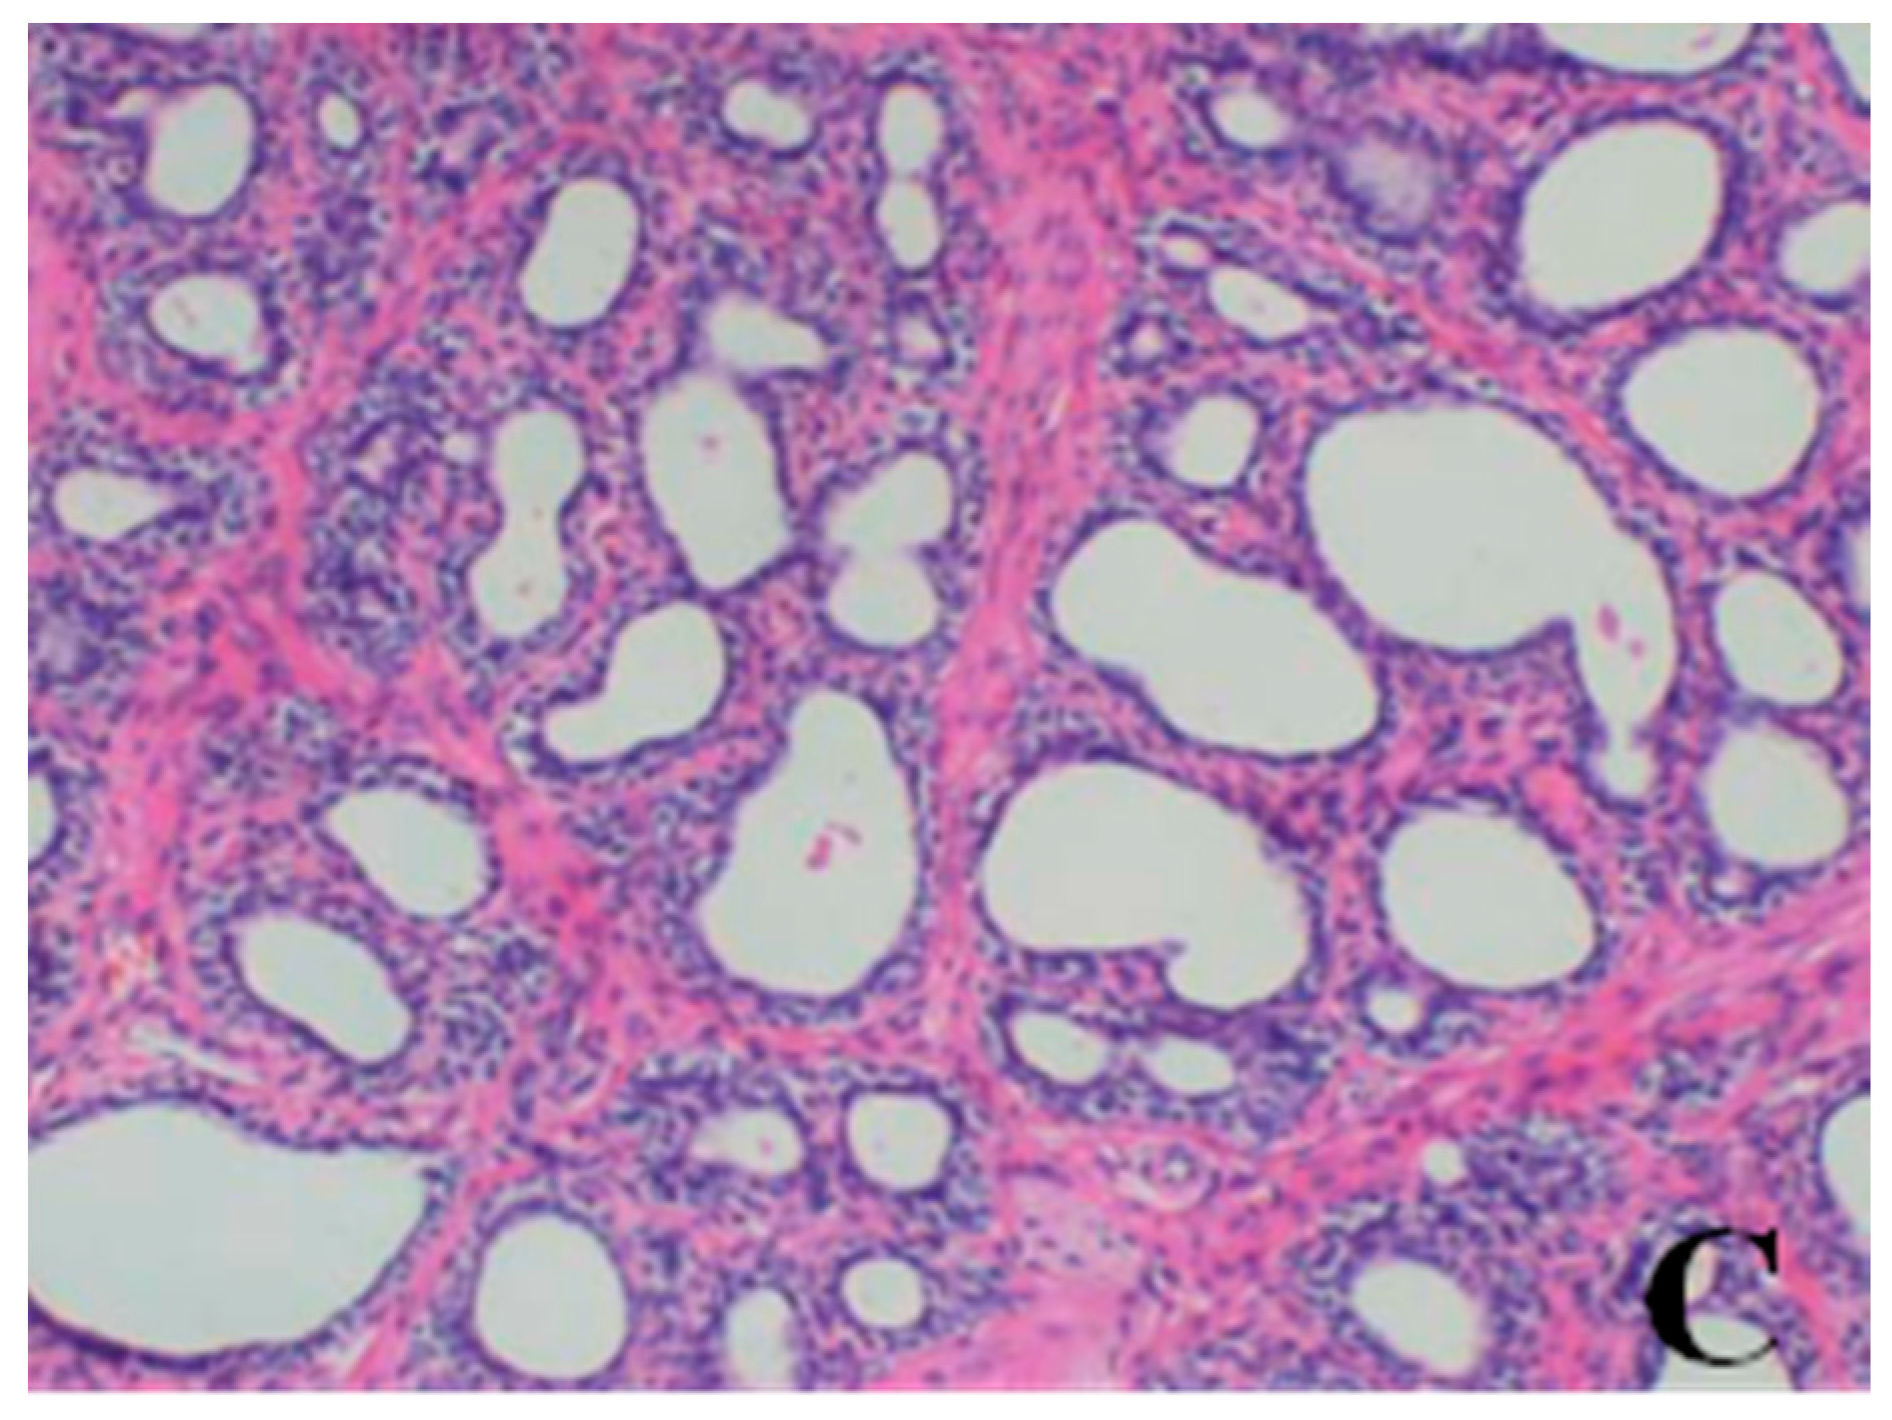

- Prostate: When compared with the control group, a reduction in the numbers and size, a thinner epithelium, narrower glandular cavity and increase in the connective tissue in the interstitium were observed in the prostatic acini of dogs in the 80- and 40-mg/kg dose groups.